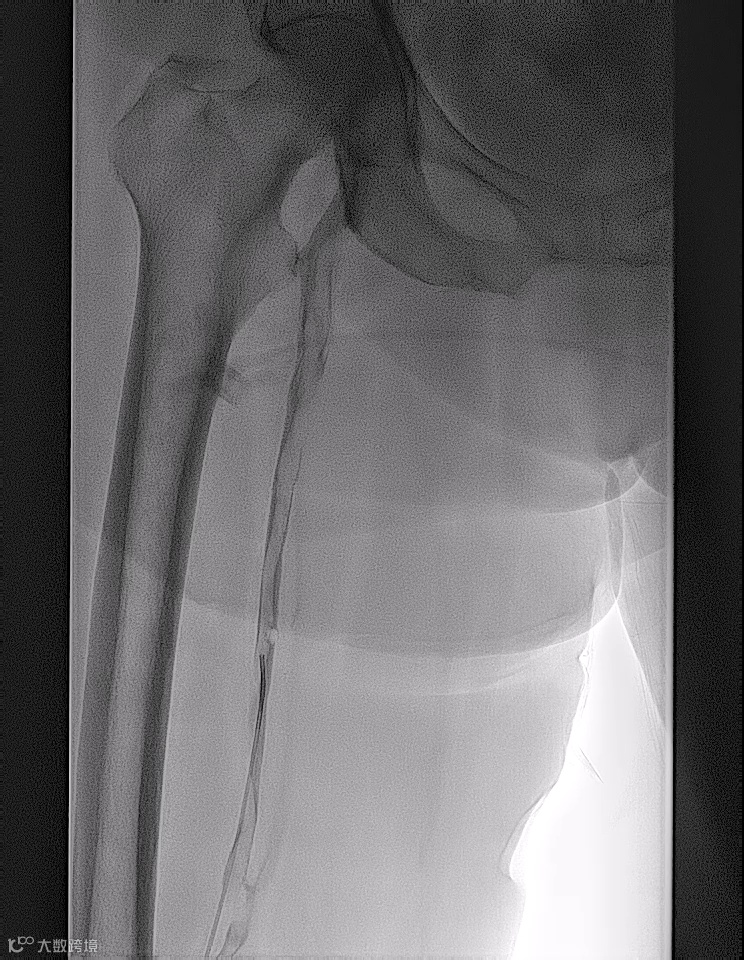

术前造影

手术过程